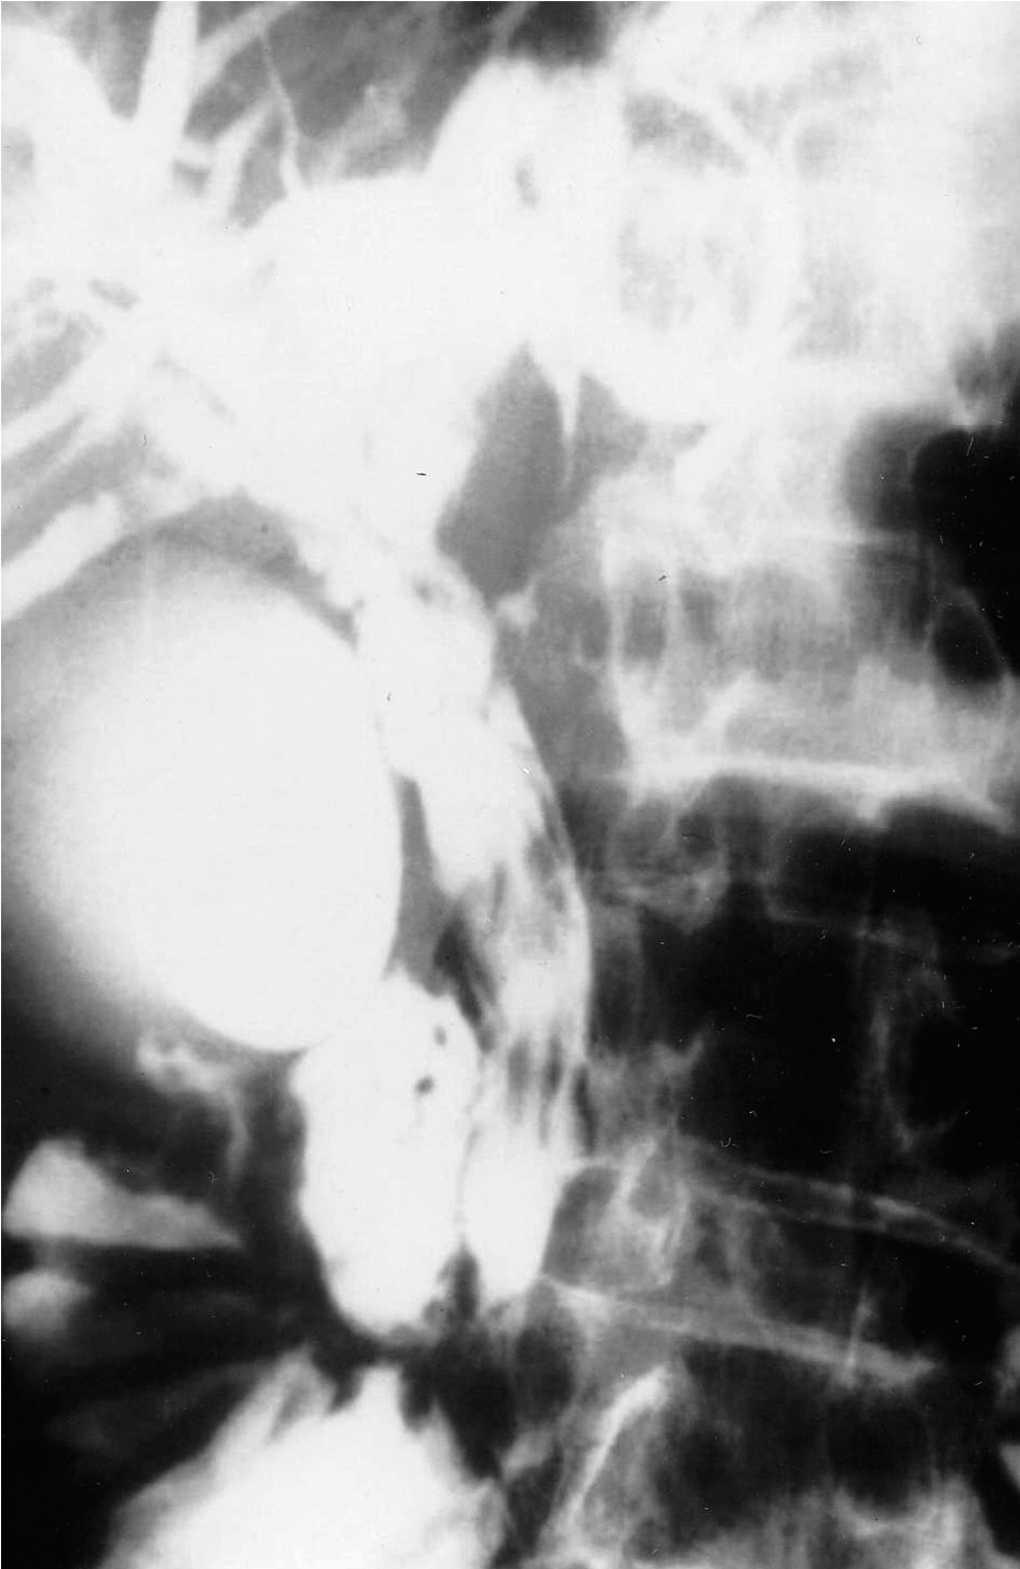

Mujer de 31 años, que es ingresada por presentar un cuadro de náuseas, vómitos y dolor epigástrico de comienzo brusco. No refiere historia de ingesta alcohólica, drogas, enfermedad litiásica biliar, traumatismo abdominal o cirugía previa. El examen físico muestra dolorimiento intenso epigástrico y descenso del peristaltismo intestinal. Los datos de laboratorio revelaron: amilasa de 502 U/l (referencia: 35-133 U/l); lipasa de 540 U/l (referencia: 7-38 U/l); fosfolipasa A2 de 580 ng/dl (referencia: 130-400 ng/dl); elastasa-I de 590 ng/dl (referencia: 0-400 ng/dl). El recuento leucocitario era de 16.400 mm3 (referencia: 3.200-8.500 mm3); la fosfatasa alcalina de 428 U/l (referencia: 98-279 U/l); la bilirrubina de 4,8/l (referencia: hasta 1 mg/dl). Los valores de BUN, creatinina, LDH y calcio se encontraban dentro de límites normales. La ultrasonografía abdominal y la tomografía computarizada demostraron aumento difuso homogéneo del páncreas. Una colangiografía mostró numerosos defectos de repleción de la vía biliar principal (fig. 1). Se realizó una colecistectomía y exploración coledociana con extracción de múltiples elementos que correspondieron a infestación por Fasciola hepatica (fig. 2). Se trató con triclabendazol en dosis única de 10 mg/kg. La paciente se encuentra libre de enfermedad pasados 5 años.

Fig. 1.